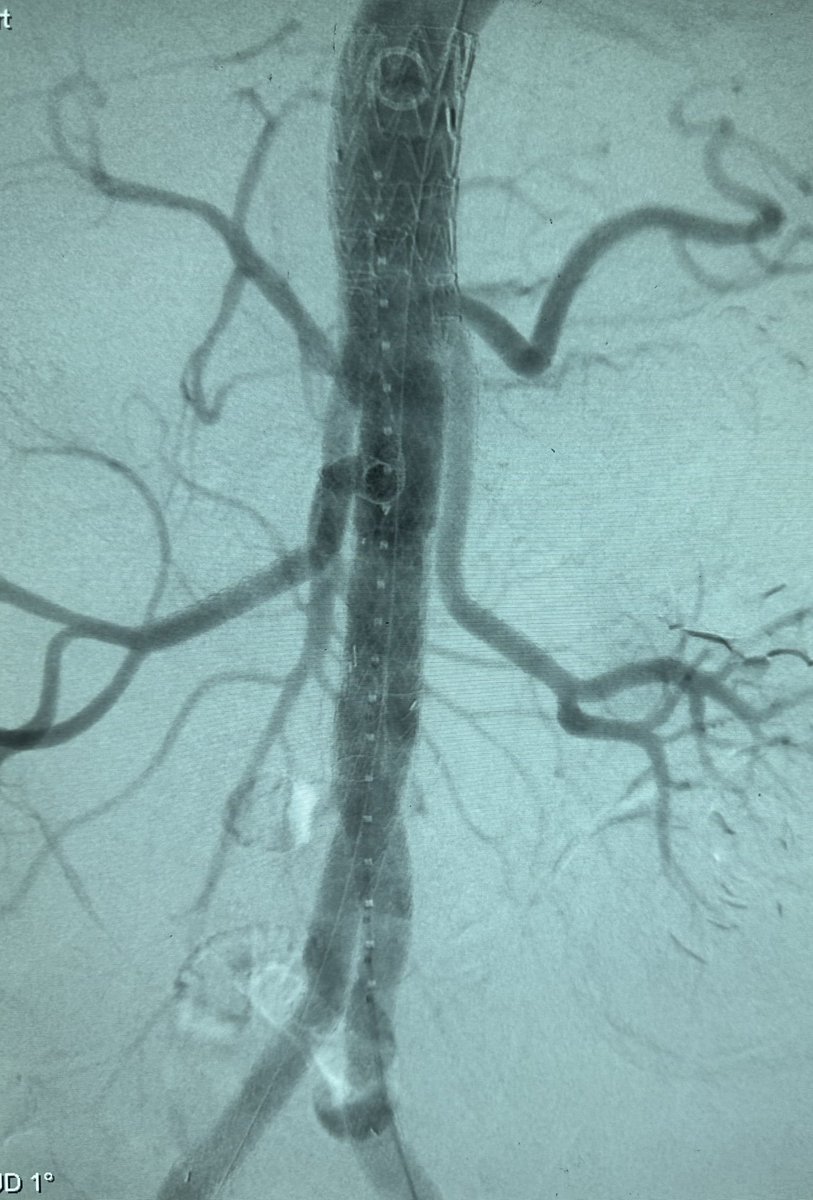

No more ‘homemade’ fenestrations, branched and off-the-shelf solutions are making complex AAA repair safer and more reproducible. Hopefully, reliance on custom-made devices will keep decreasing as technology advances.

#AorticSurgery #Innovation #VascularSurgery #BEVAR